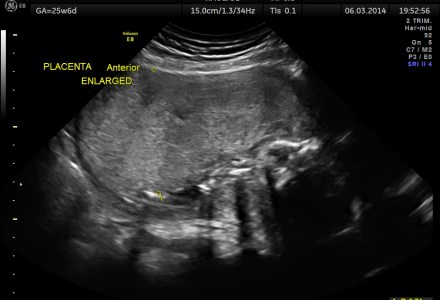

IUGR – PLACENTOMEGALY – ABNORMAL DOPPLER – UTERO PLACENTAL INSUFFICIENCY